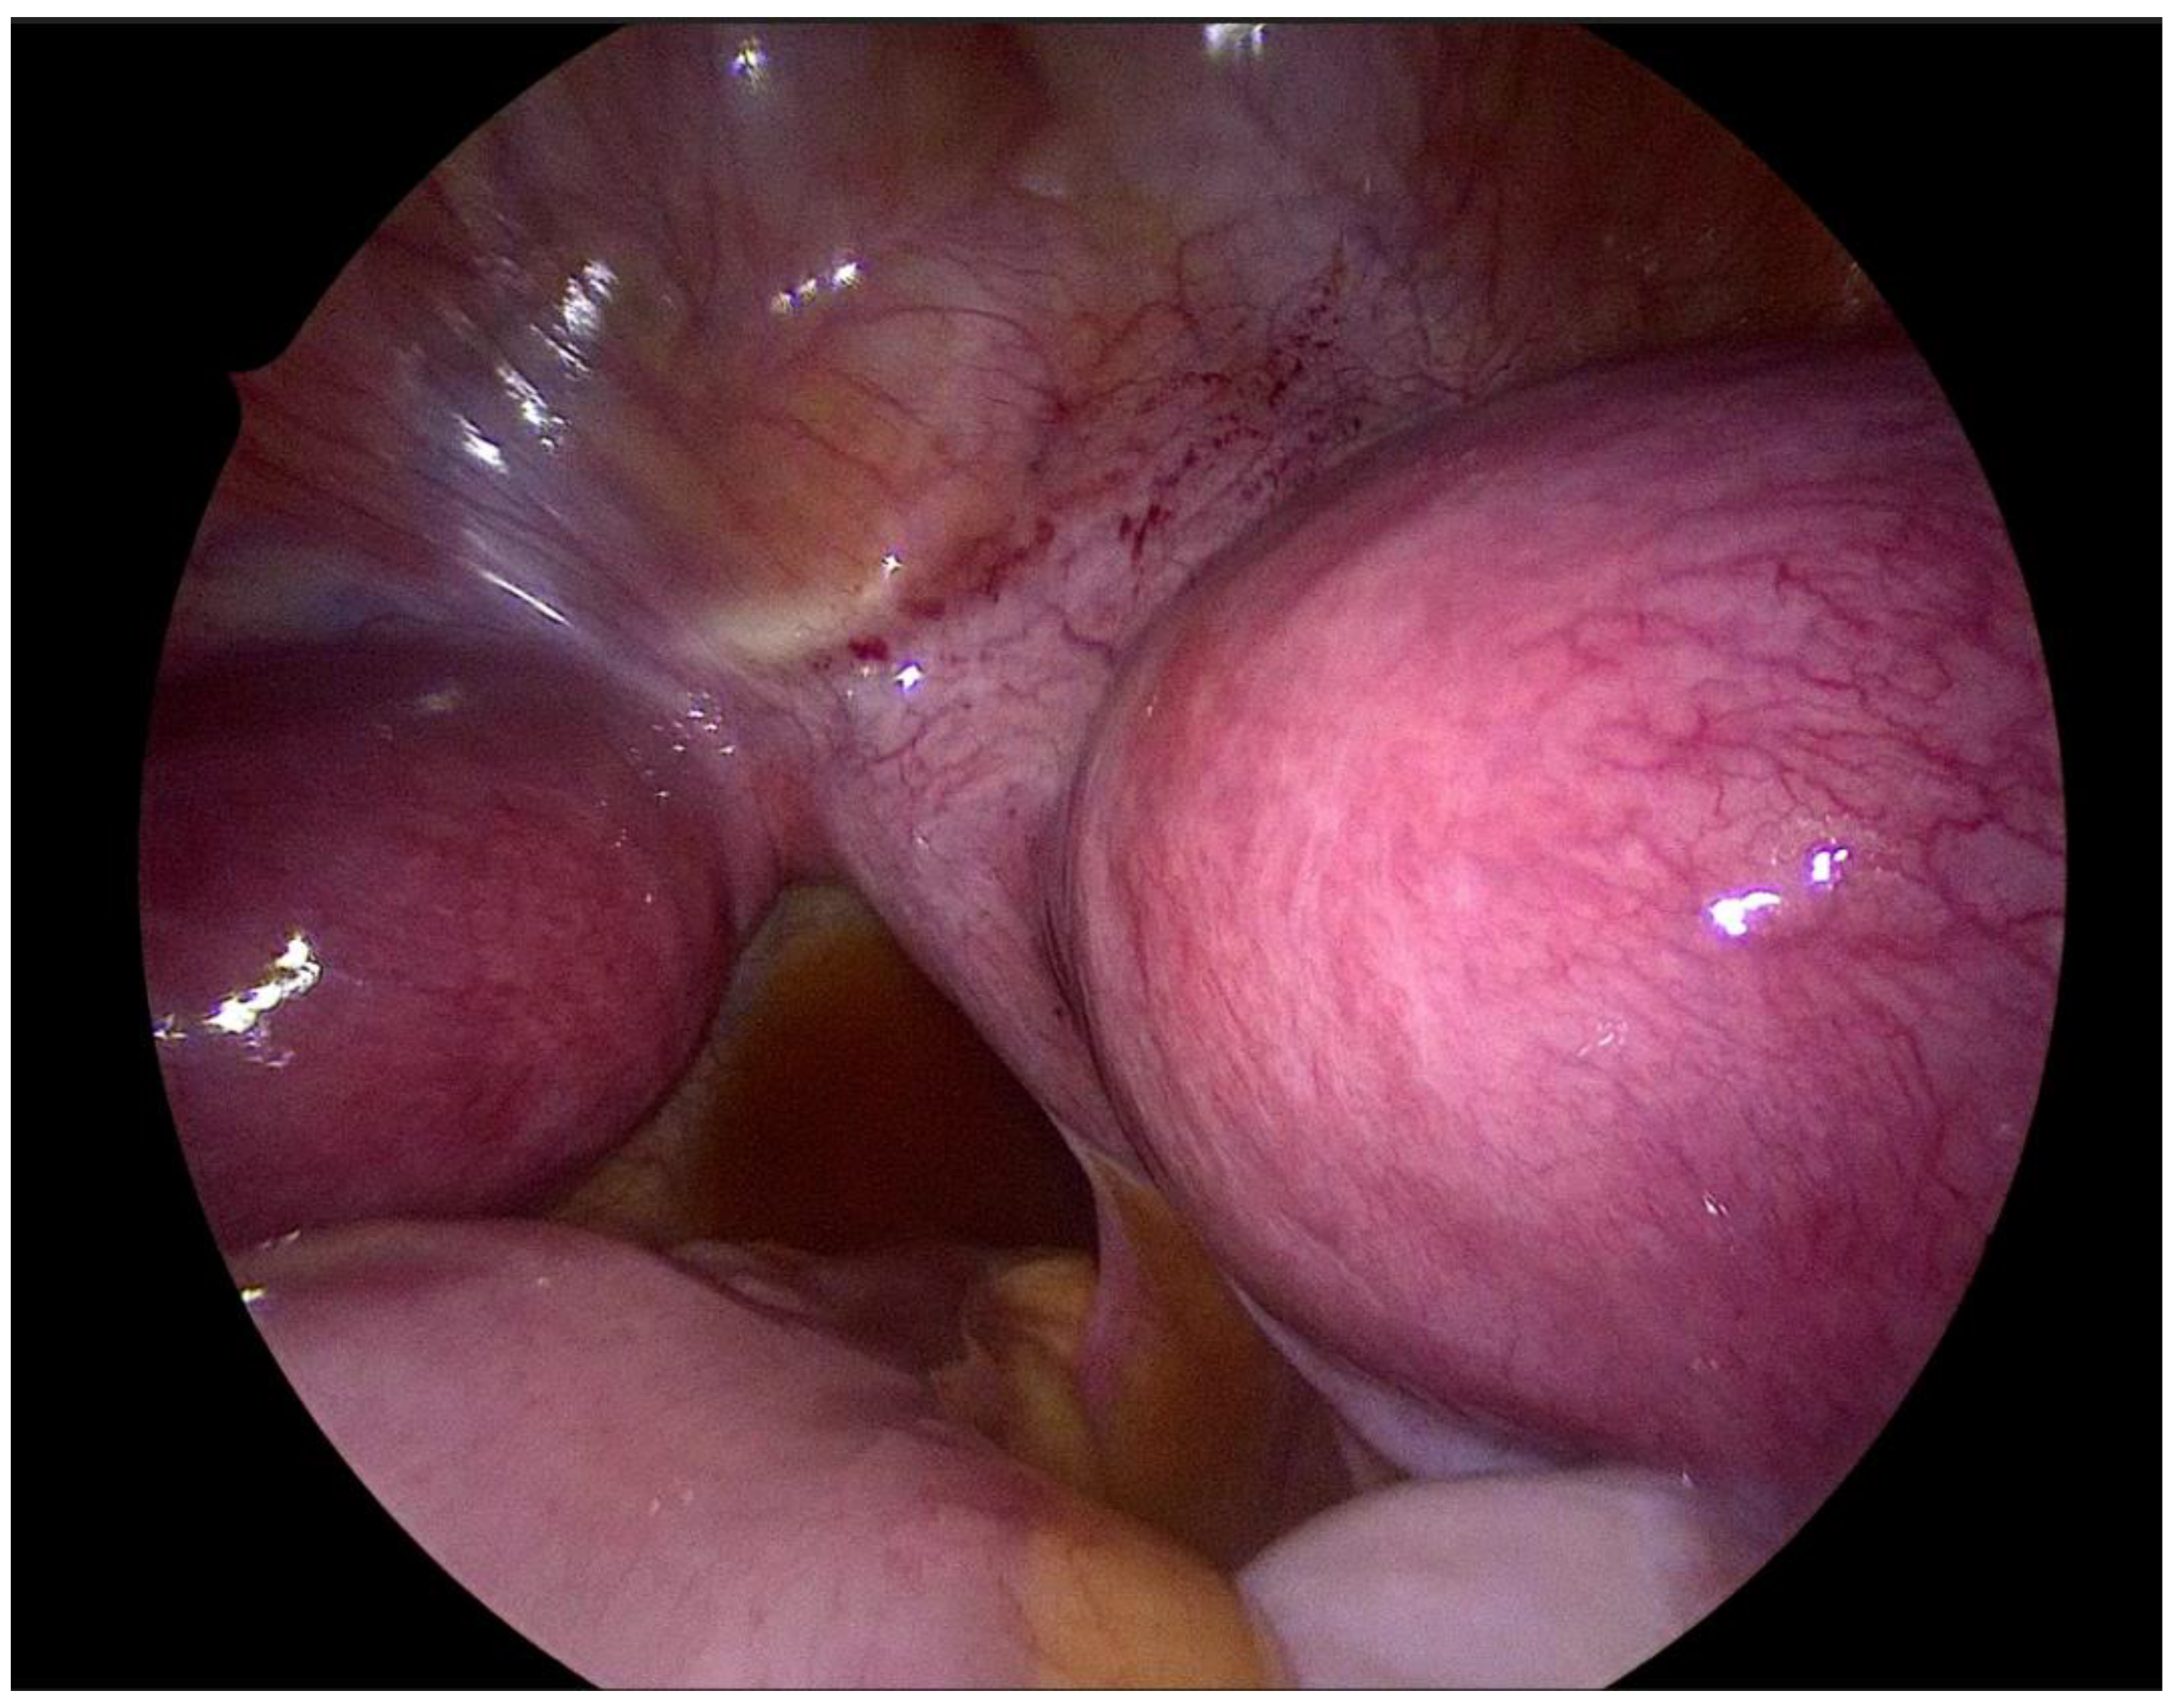

Step 3 Surgical management Surgery is necessary when acute abdominal symptoms are present. “Wait and see” approach is only possible when the clinical situation allows it. Perform laparoscopy and vaginoscopy in order to achieve the correct diagnosis and treat concomitant hematosalpinx and endometriosis [14]. Intraoperative US is helpful to evaluate the place of resection. Unnecessary lengthening the time to diagnosis, contributes to unindentent consequence. |

Step 4 Postoperative management The insertion of uterine catheter filled with saline into a place of stenosis allow to avoid the risk of possible restenosis [15]. Continuous oral contraceptives are recommended to avoid possible consequences like the risk of restenosis. |